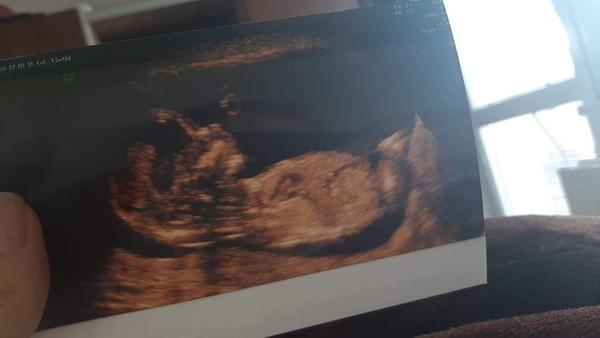

Screening 16.tt. Co myslíte, že budu mít?

Ahoj co myslite ze budu mit?doktorka mi rikala, ze nerika nikdy pohlavi.

@elen29 Dyt na te fotce nejde videt do mist, kde pohlavi je, tak co tu mame zkoumat? 😀

Ledaze by tu pipku nebo kulky melo na hlave 🤷🏼‍♀️